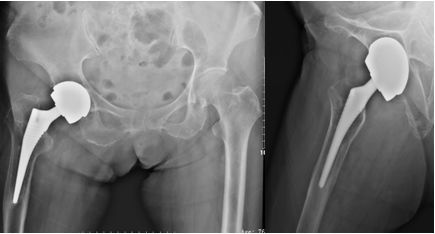

图4 76岁,女性患者,9年前于外院行全髋关节置换术,术后恢复良好;2年前开始出现疼痛,近半年无法行走,需轮椅代步。

图5 翻修术后髋关节假体稳定,假体位置角度良好,可早期下地活动锻炼